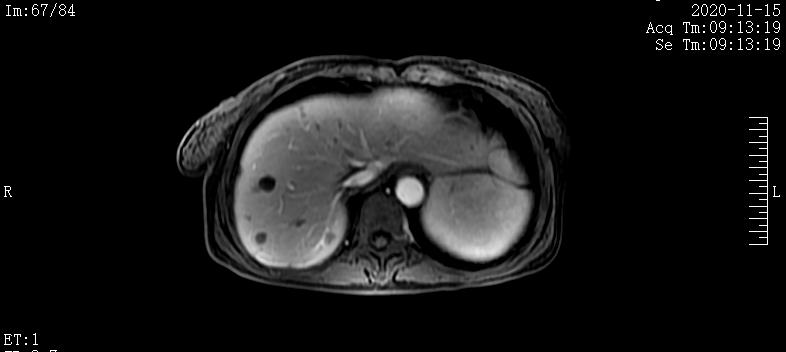

2020-4-20肝脏MRI提示:肝内多发团块,肝门及腹膜后淋巴结肿大;胰腺体尾部团块

2020-6-17肝脏MRI提示:1.胰腺体尾部异常信号,较前略缩小。2.肝内多发结节及团块,考虑转移瘤,部分病灶较前缩小。3.腰1-3椎体异常信号强化范围较前略缩小

2020-8-22肝脏MRI提示:1.肝脏多发异常信号,较前稍缩小。2.腰椎内异常信号,较前缩小

2020-11-15